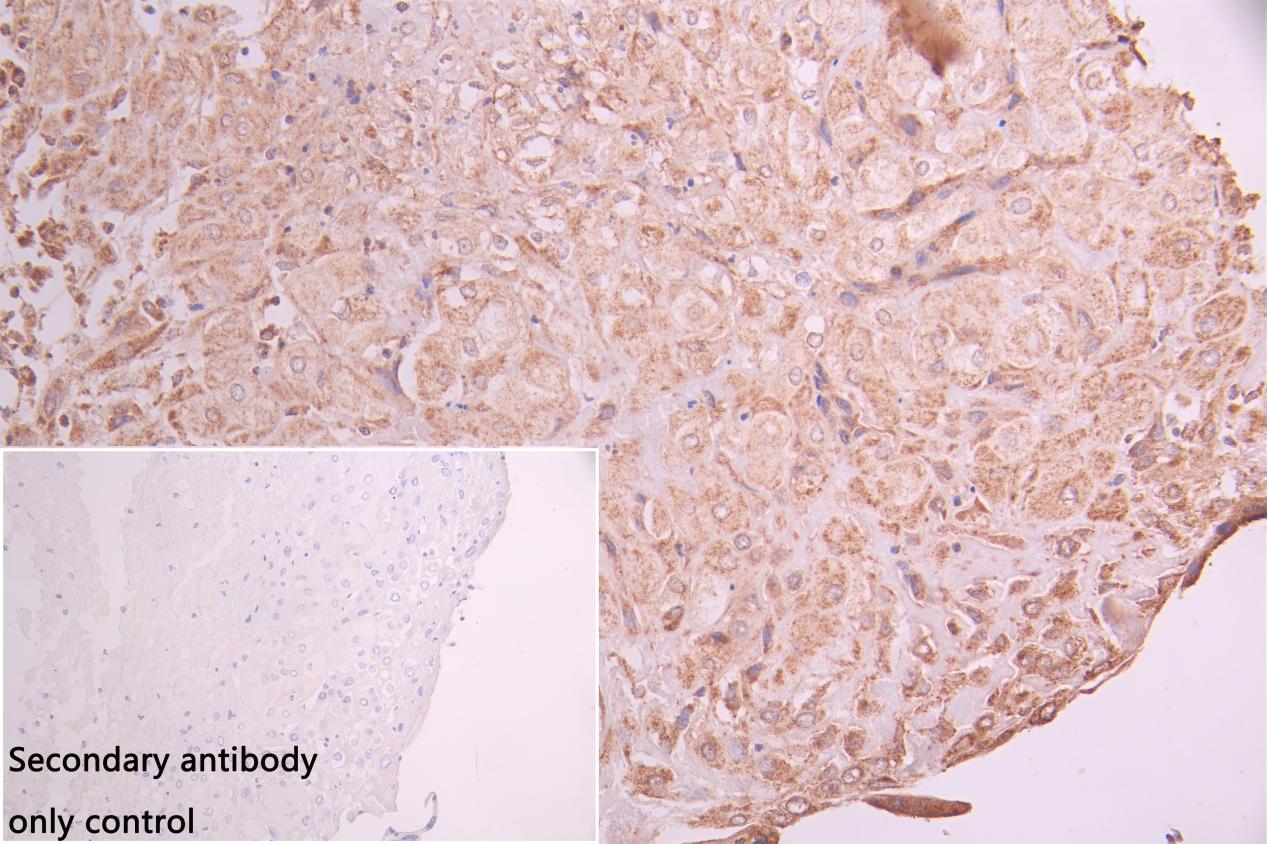

IHC image of CSB-RA191985A0HU diluted at 1:100 and staining in paraffin-embedded human liver cancer performed on a Leica BondTM system. After dewaxing and hydration, antigen retrieval was mediated by high pressure in a citrate buffer (pH 6.0). Section was blocked with 10% normal goat serum 30min at RT. Then primary antibody (1% BSA) was incubated at 4°C overnight. The primary is detected by a Goat anti-rabbit IgG polymer labeled by HRP and visualized using 0.05% DAB.